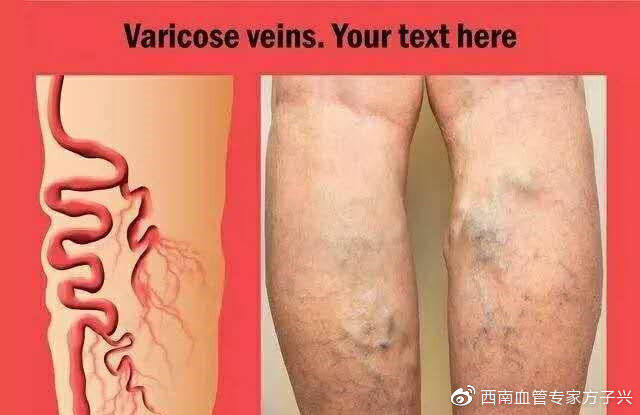

静脉曲张

静脉曲张

腿部静脉曲张静脉

腿部静脉曲张静脉